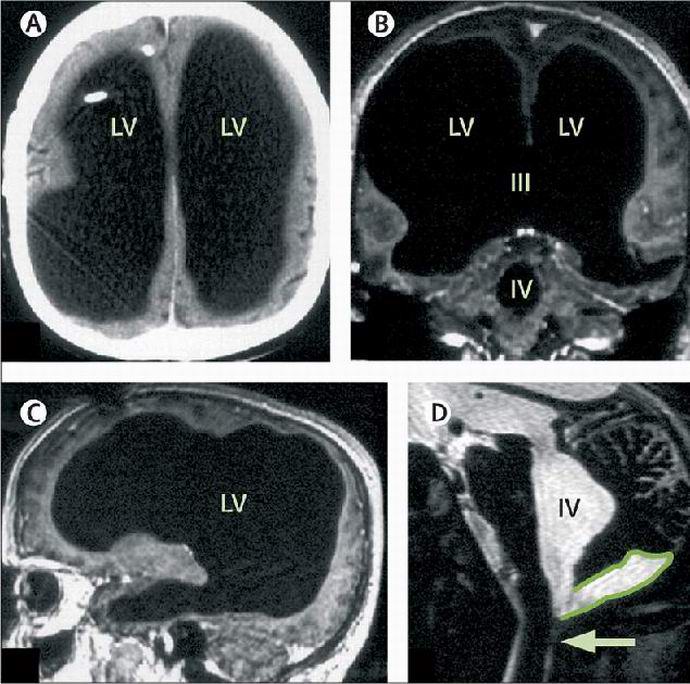

Amikor az orvosok elérték a Mathieu agyi vizsgálatát, kiderült szó szerint sokkolt. A férfi agya olyan kicsi volt hogy a képeken ez gyakorlatilag nem volt észrevehető. Egy sorozat után tesztek, az orvosok megállapították, hogy a cerebrospinális folyadék, kering az egészséges emberben az agyban és kiválasztódik a testben keringési rendszer, megtöltötte a beteg koponyáját, így távozott nagyon kis mennyiségű szürke anyag. Struck ezzel a leletszakértők megértették a jelenség természetét és megállapította, hogy gyermekkorban egy embert hidrocephalusa miatt kezeltek – egyéb szóval, az agyából fölösleges folyadékot szivattyúzták ki. Ehhez, orvosok Mathieu-nak volt egy shuntje, majd eltávolította a shuntot. De amint láttam, az ezt követő probléma nem tűnt el.

Fél évszázad alatt a folyadék felhalmozódott a koponyába A francia doboza kihúzta az agyát. Csodálatos, de fájdalom a lábakban lett az első, és eddig az egyetlen komplikáció, amely társult egy betegség. Az elmúlt nyolc évben a tudósok gondosan megvizsgálták a testet. Mathieu. Állítólag az agy apró méretű a hidrocephalus következménye, hogy az ember csendesen él ezek az évek valódi rejtély.